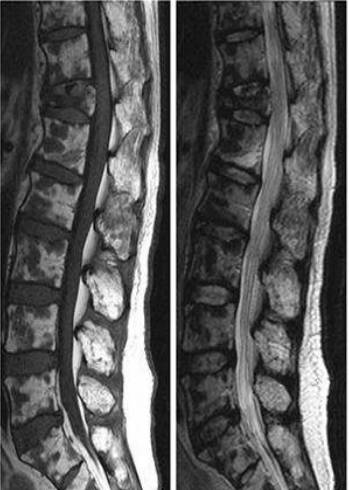

天津市肿瘤医院血液科与放射科合作,开展了全身低剂量CT在多发性骨髓瘤中应用的临床试验,欢迎广大患者积极入组。MRI和PET/CT的敏感性和特异性均较高,且功能性成像可以反映肿瘤负荷与肿瘤细胞的代谢活性,是更为准确的检测手段,研究表明MRI和PET/CT上的变化均与实验室检查有一定关联,并可用于疗效评价等。MRI对软组织和骨髓的分辨率很高,是检测弥漫性骨髓浸润和压缩性骨折的最敏感的手段,MRI还可以区分骨质疏松的良恶性,以此来评估骨折风险,但MRI检查时间长,不能用于有幽闭恐惧症、金属物和假体的患者,对于整个骨骼系统的视野较局限。18F-FDG PET/CT虽然对脊柱的敏感性不如MRI,但具有可以在出现溶骨性病变之前就反映出新陈代谢的变化,能够直观地显示出肿瘤负担的优势。

图3.MRI显示MM患者的脊柱病变(左T1,右T2)